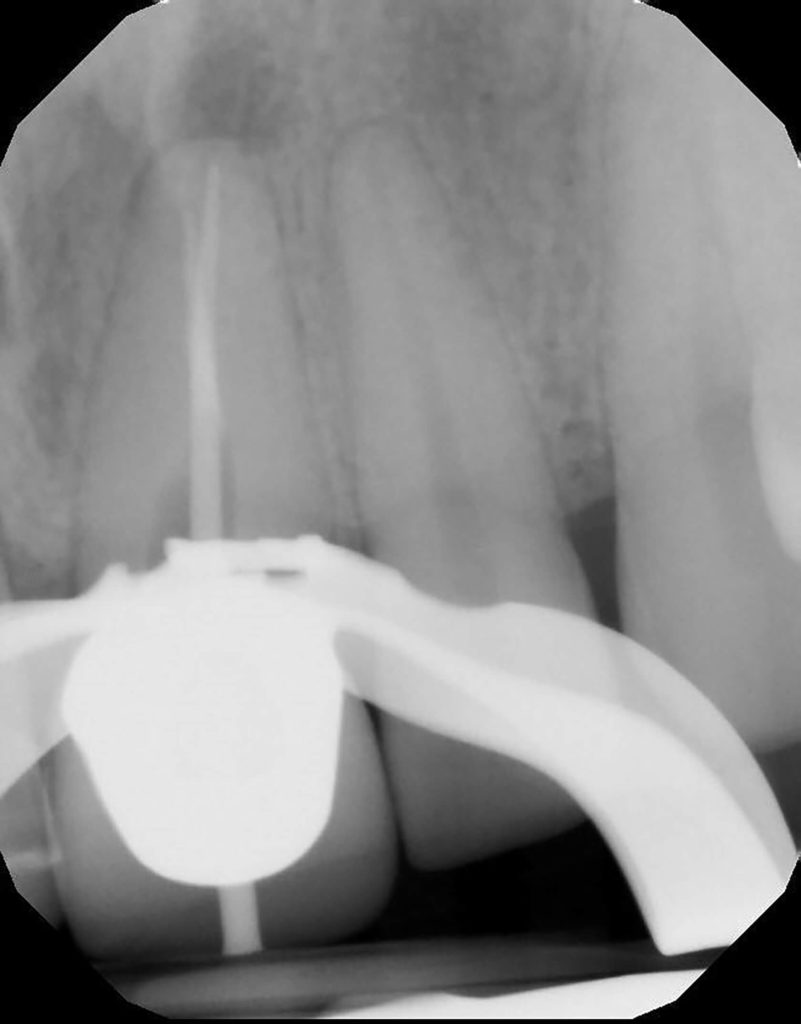

Fun retreatment. Patient had RCT on 9, which was retreated by another endodontist 5 years ago. Patient developed pain and swelling in the area. CBCT revealed a transported canal with a perforation. I was able to locate the canal and hopefully save the tooth!